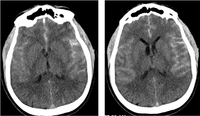

CT brain showing subarachnoid hemorrhage from a ruptured posterior cerebral artery aneurysm (2 of 2)

Courtesy of Dr Salah Keyrouz; used with permission

CT brain showing subarachnoid hemorrhage from a ruptured posterior cerebral artery aneurysm (1 of 2)